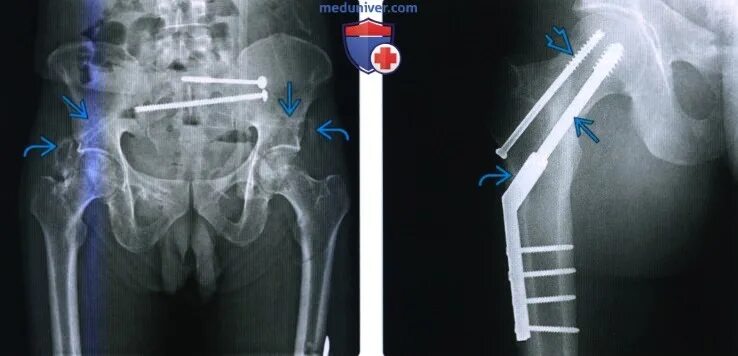

Операция тазобедренного сустава у взрослых